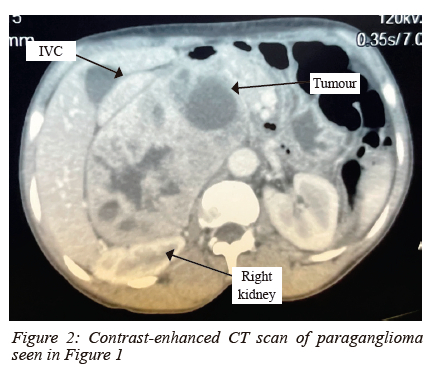

Of the 11 paragangliomas, 7 were not candidates for laparoscopy (Figures 1 and 2) and 4 were converted to laparotomy.

Overall, 43.1% (19/44) of the procedures were completed laparoscopically. Of the 27 cases eligible for laparoscopy, 70.3% (19/27) were completed successfully and 29.6% (8/27) were converted to laparotomy. All conversions were via a subcostal incision except in one patient where a right thoracotomy was indicated for an intrathoracic paraganglioma that was reported on computed tomography scan (CT scan) as a right adrenal mass. The 17 planned laparotomies were via a midline incision (Figure 1).

Furthermore, paragangliomas are often challenging to excise via laparoscopy due to their unpredictable blood supply, altered anatomy and the vicinity of major vasculature.13